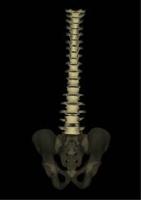

また、擬似的に三次元画像を作成することで、立体的に椎体の配列を観察することも可能です。